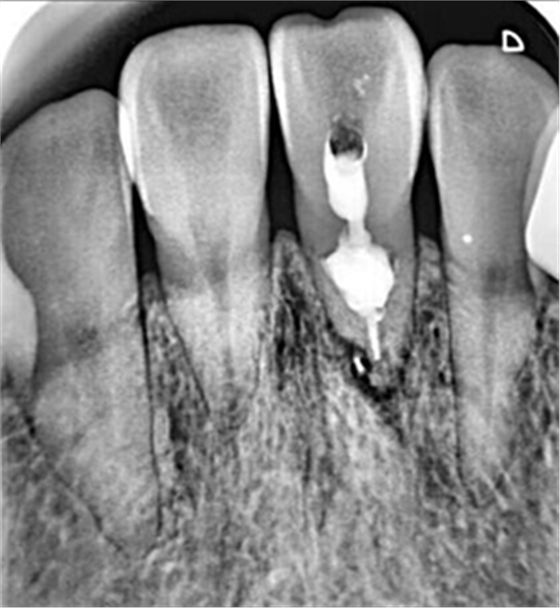

牙內(nèi)吸收一旦確診,則需要對(duì)患牙的預(yù)后做出判斷。對(duì)于有保留價(jià)值的患牙,應(yīng)該及時(shí)行根管治療。對(duì)于未發(fā)生根管側(cè)穿者,應(yīng)完全去除根管內(nèi)吸收組織,以防止其牙體硬組織的進(jìn)一步破壞。牙內(nèi)吸收所導(dǎo)致的病損的特點(diǎn),給根管治療帶來(lái)了難度。行根管預(yù)備時(shí),應(yīng)盡量保守,以最大程度的保留牙體組織,以免對(duì)本就薄弱的根管壁造成進(jìn)一步的損害。對(duì)于有活動(dòng)性吸收的患牙,在治療過(guò)程中,炎癥牙髓和肉芽組織可能出現(xiàn)大量的滲血從而影響操作視野。同時(shí),機(jī)械預(yù)備的方法往往不能完全達(dá)到吸收所造成的缺損部位。因此,根管預(yù)備時(shí)次氯酸鈉和超聲設(shè)備的作用就顯得尤為重要。次氯酸鈉可以溶解壞死的牙髓組織。超聲的震蕩可以使次氯酸鈉沖洗液活化,并充分滲透到根管系統(tǒng)的每個(gè)角落,以減少根管內(nèi)細(xì)菌的數(shù)量。然而,即使使用了超聲設(shè)備,往往根管內(nèi)局部還是會(huì)有細(xì)菌的殘留因此,根管內(nèi)封藥應(yīng)該具有良好的抗菌作用,以提高器械所不能到達(dá)部位的消毒。氫氧化鈣糊劑對(duì)根管內(nèi)多種細(xì)菌有殺傷作用,并可滲入牙本質(zhì)小管發(fā)揮殺菌作用,效果明顯。此外有研究證實(shí),氫氧化鈣與次氯酸鈉有協(xié)同作用,可減少根管內(nèi)有機(jī)碎屑的殘留囚。對(duì)于根管的充填,應(yīng)選擇具有良好流動(dòng)性的充填材料,來(lái)封閉吸收所造成的缺損。其中,熱塑性牙膠充填技術(shù)最為常用。

在一些病例中,牙內(nèi)吸收己經(jīng)發(fā)展至牙根外表面,使得根管與牙周相連通,并可能出現(xiàn)鄰近牙周組織的病變。這就需要在根管治療的同時(shí)行穿孔的修補(bǔ)。礦物三氧化物凝聚體(mineraltrioxideaggregate,MTA)具有良好的生物相容性和誘導(dǎo)成骨性,對(duì)根尖周組織的刺激小,并且和其他材料相比,其封閉性也更好,故常用來(lái)做穿孔的修補(bǔ)。當(dāng)牙內(nèi)吸收的缺損不可修復(fù)時(shí),則只有選擇拔除。